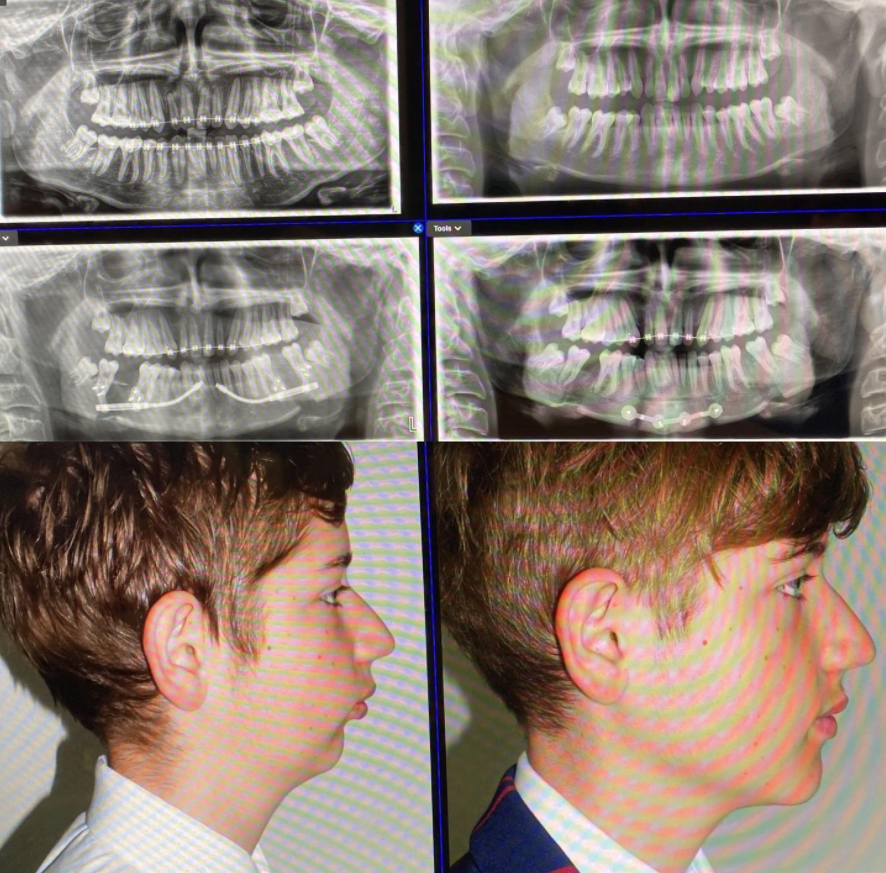

RESULTS:

View attachment 2614675

View attachment 2614678